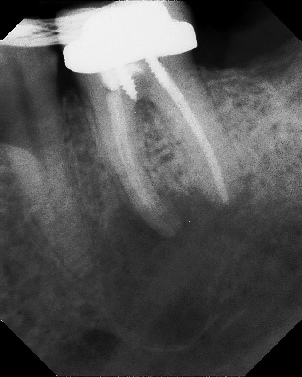

COMPLICATED ANATOMY LARGE LESIONS CALCIFIED CANALS PERFORATION / RESORPTION SEPARATED INSTRUMENTS SURGICAL CASES RETREATMENT / pOST REMOVAL OPEN APICES ACCESS THRU CROWNS Root Canal Case Portfolio